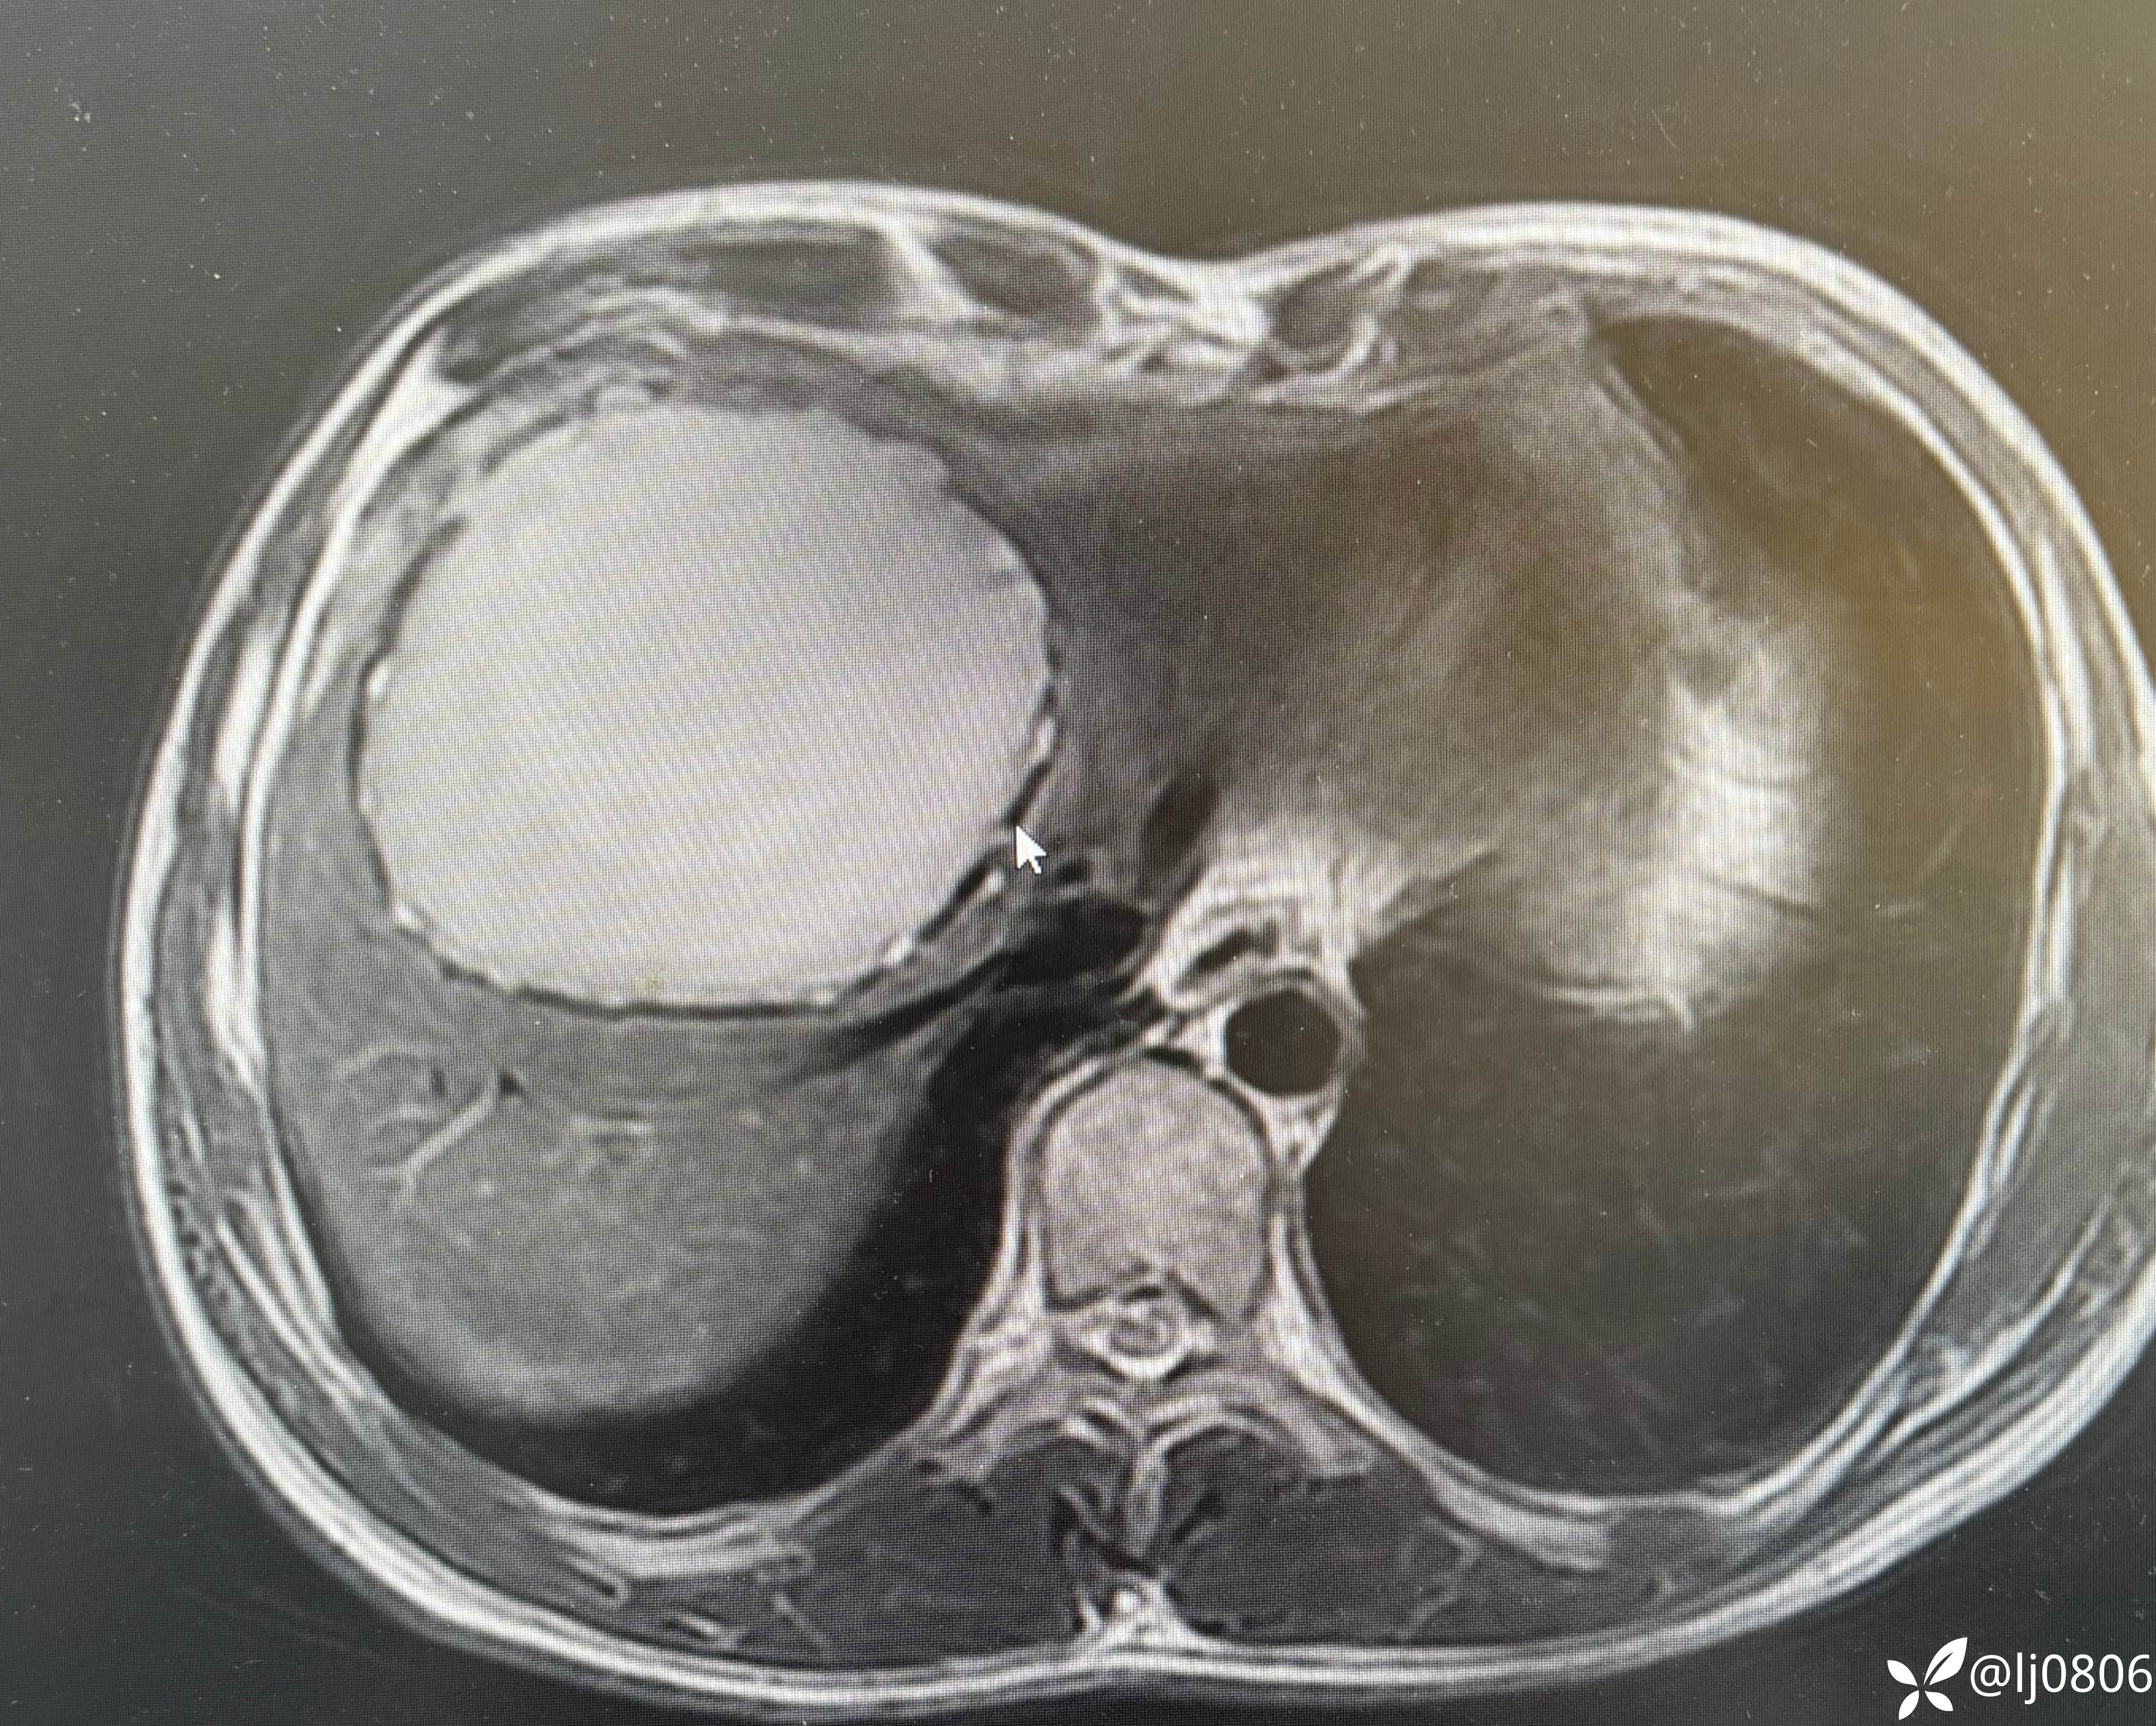

同道教授做的包虫根治术

还是牛,地方特色,将来有可能机器人拿下的空白领域: